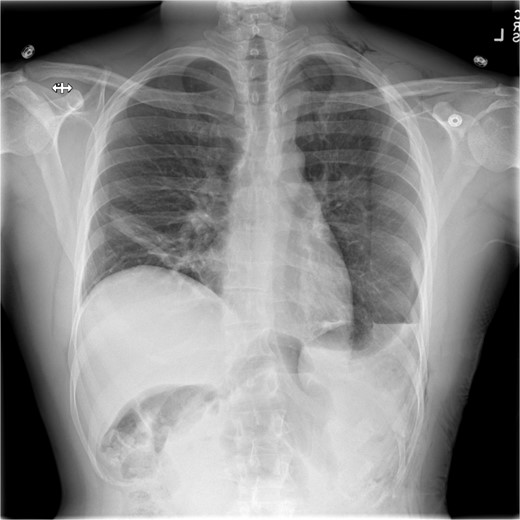

This is a case of a 26-year-old male patient who presented with symptoms of dyspnea on exertion, left chest pressure, and constipation for 7 years. He was a never smoker with no history of trauma, nor prior neck and chest surgeries. Baseline pulmonary functions tests revealed FEV1 of 71% predicted and DLCO of 77% predicted. Work-up included a computed tomography (CT) of the chest which revealed marked left hemidiaphragm elevation with compression atelectasis of the left lower lobe (Fig. 1). A fluoroscopic sniff test showed paradoxical movement of the left hemidiaphragm consistent with diaphragmatic paralysis. Interestingly, abdominal imaging obtained 14 months before surgery showed a displaced stomach but without volvulus (Fig. 2). Due to the impact on the patient’s quality of life, he was offered surgical treatment with a robotic-assisted left thoracoscopic plication of the diaphragm. This was done using a three-arm technique using the Da Vinci Xi surgical system (Intuitive Surgical, Sunnyvale, CA) with an additional assistant port. Plication was performed by placing multiple horizontal mattresses sutures reinforced with pledgets in an anterior–posterior orientation, and systematically working medial to lateral. A postoperative chest X-ray showed a satisfactory result (Fig. 3).

Immediate post-operative film demonstrates intact repair, and well-positioned chest-tube.